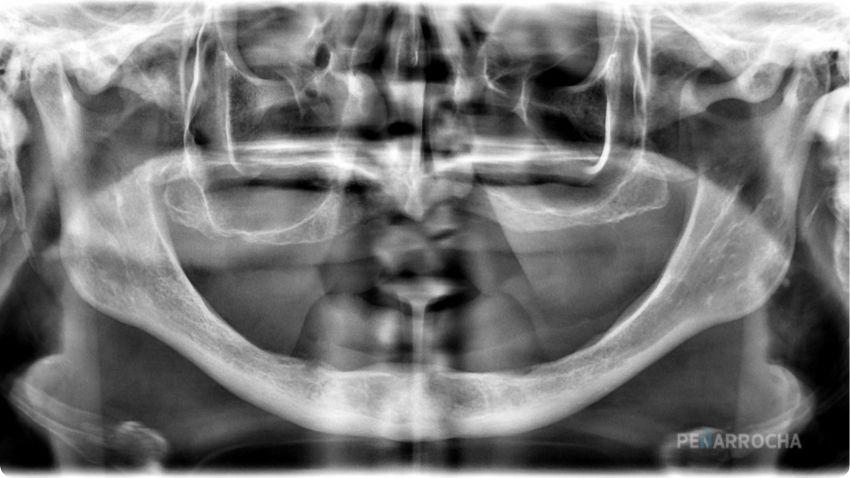

Evaluación y planificación digital

Se realiza un estudio radiológico con CBCT para analizar la anatomía del hueso cigomático y planificar la posición de los implantes.

Se utiliza cirugía guiada y modelos estereolitográficos en 3D para ensayar la intervención y aumentar la precisión quirúrgica.